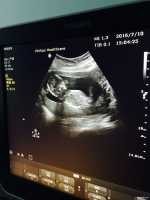

三胎妈咪超清晰B超图,很明显的小jj哦

我是一个三胎妈妈,前面两个是可爱的小公主,但就是想儿女双全,所以拼三,老天爷很眷顾我,三胎总于如愿,我是103天做的B超,看的很清晰,下面说说怀男女不同的症状。 1.怀女宝时就是恶心,基本不吐,不到三月基本就没反应了,怀这个也是很恶心,吐的比较多,到现在还有反应 2.怀女宝是排卵10天后才册出来意念水印,怀这个第八天就有水印了。 3.怀女宝时排卵以后没什么感觉,就是有点胸涨吧,怀这个排卵以后也是胸涨,腰酸,屁多,而且容易口渴。 4.在有就是胎梦,怀女宝没记得做过什么梦,但怀这个梦见过黄瓜,枣树,生男孩还看见小j j了,反正梦到过好多蔬菜,个人觉得胎梦挺准的。只是个人感觉哦! 因为现在才15周,所以这都是前期症状,每个人体质不一样可能症状也不一吧,我把我的给大家分享一下,希望姐妹们想男得男,想女得女。最后发上刚照的B超图